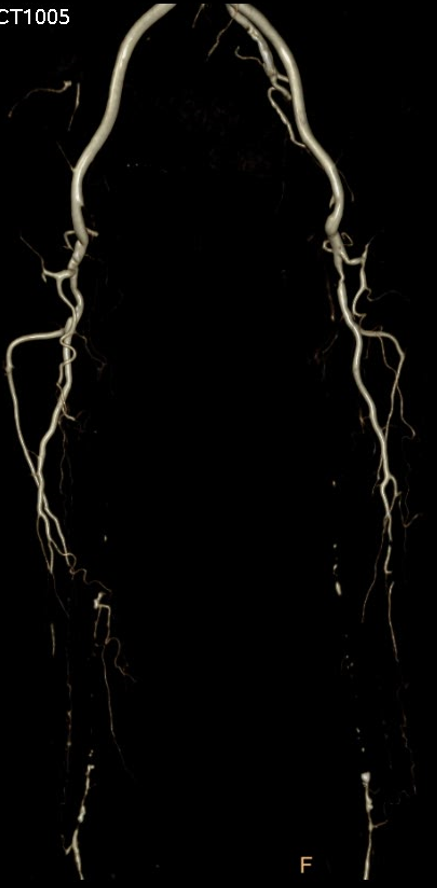

★ Case 5

Female,82 y

Severe claudication over 1 year in both extremities esp. in the left

DM over 10 years

CTA:SFA-PA long CTO

左右滑动查看